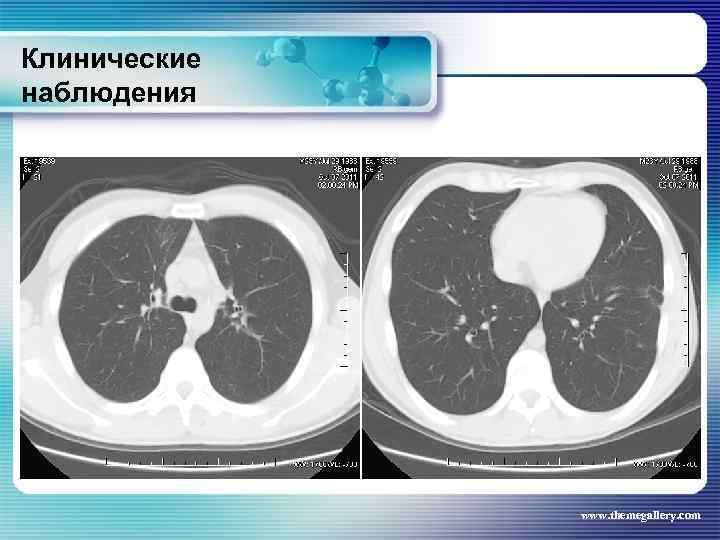

Клинические наблюдения Больной М. , 22 лет Заболел в январе 2010 года, когда появился мучительный кожный зуд, похудание, прогрессивный рост лимфатических узлов на шее, затрудненное дыхание. Самостоятельно обратился в поликлинику, направлен в гематологическое отделение. Выполнена биопсия шейного лимфатического узла: Лимфома Ходжкина. , нодулярный склероз Grade I. Уже отделении появилась лихорадка. При лабораторном обследовании выявлены признаки выраженной активности процесса. Результаты лучевого обследования: www. themegallery. com

Клинические наблюдения Больной М. , 22 лет Заболел в январе 2010 года, когда появился мучительный кожный зуд, похудание, прогрессивный рост лимфатических узлов на шее, затрудненное дыхание. Самостоятельно обратился в поликлинику, направлен в гематологическое отделение. Выполнена биопсия шейного лимфатического узла: Лимфома Ходжкина. , нодулярный склероз Grade I. Уже отделении появилась лихорадка. При лабораторном обследовании выявлены признаки выраженной активности процесса. Результаты лучевого обследования: www. themegallery. com